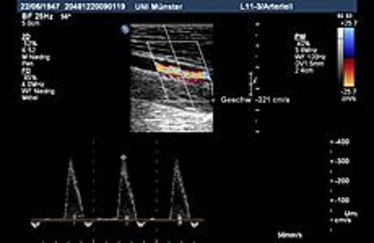

Münsteraner Ultraschall-Workshop: Refresherkurs Spezielle Neurologische Ultraschalldiagnostik

Münsteraner Ultraschall-Workshop: Refresherkurs Spezielle Neurologische Ultraschalldiagnostik